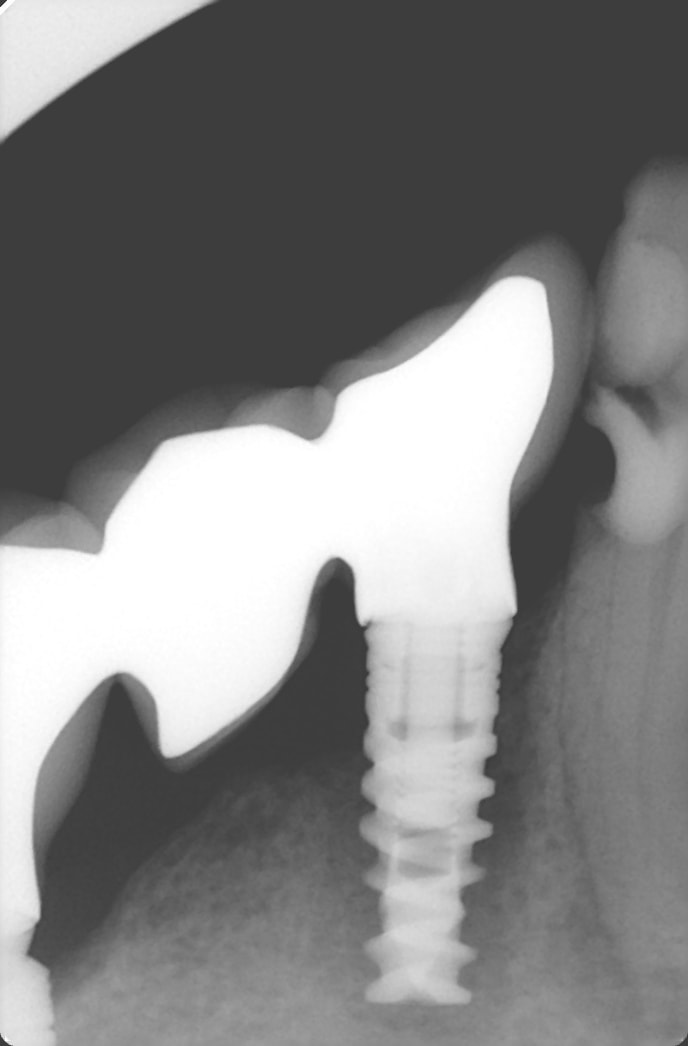

allez ne soyons pas sectaire que j'me dis. Si Enlaye le fait avec les dents, pourquoi pas avec un implant.

patient que je reçois en mai dernier , 93 ans, aucune hygiène, et beaucoup de soins dentaires. il vient pour autre chose, mais me parle aussi de son bridge mandibulaire droit qui bouge. je touche à peine et je me retrouve avec le bridge dans la main. le pilier distale est descellé, mais en mesiale j'ai l'implant qui vient avec le bridge. un coup de rincette avec la seringue du fauteuil, un peu de ciment en distal et je repose le tout dans l’alvéole. je revois le patient plus tard pour faire l'endo sur la 43..

la première radio date de mai, la deuxième a été faite cette semaine .

maintenant, l'augmentation de la densité osseuse est peut être une illusion du à la radio..